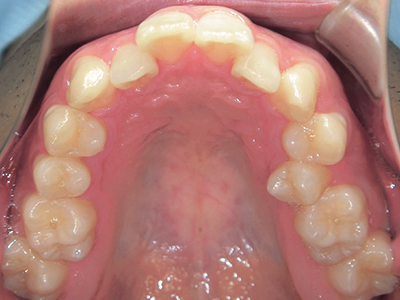

ないき歯科クリニックでは、上あごの成長不足を補い、鼻呼吸を獲得しつつ歯列を整え、将来のお口をより健康な状態にすることをゴールに定める矯正治療をおこなっています。

【4】矯正治療

矯正装置を装着し、調整しながら少しずつ歯を移動させ、歯並びを整えていきます。

状態によって家庭でのトレーニングが必要な場合もあり、治療期間も個人差があります。

あくまでも平均値ではありますが、一般的には月1回程度来院頂き、1~2年程度を目安に治療を進めていきます。